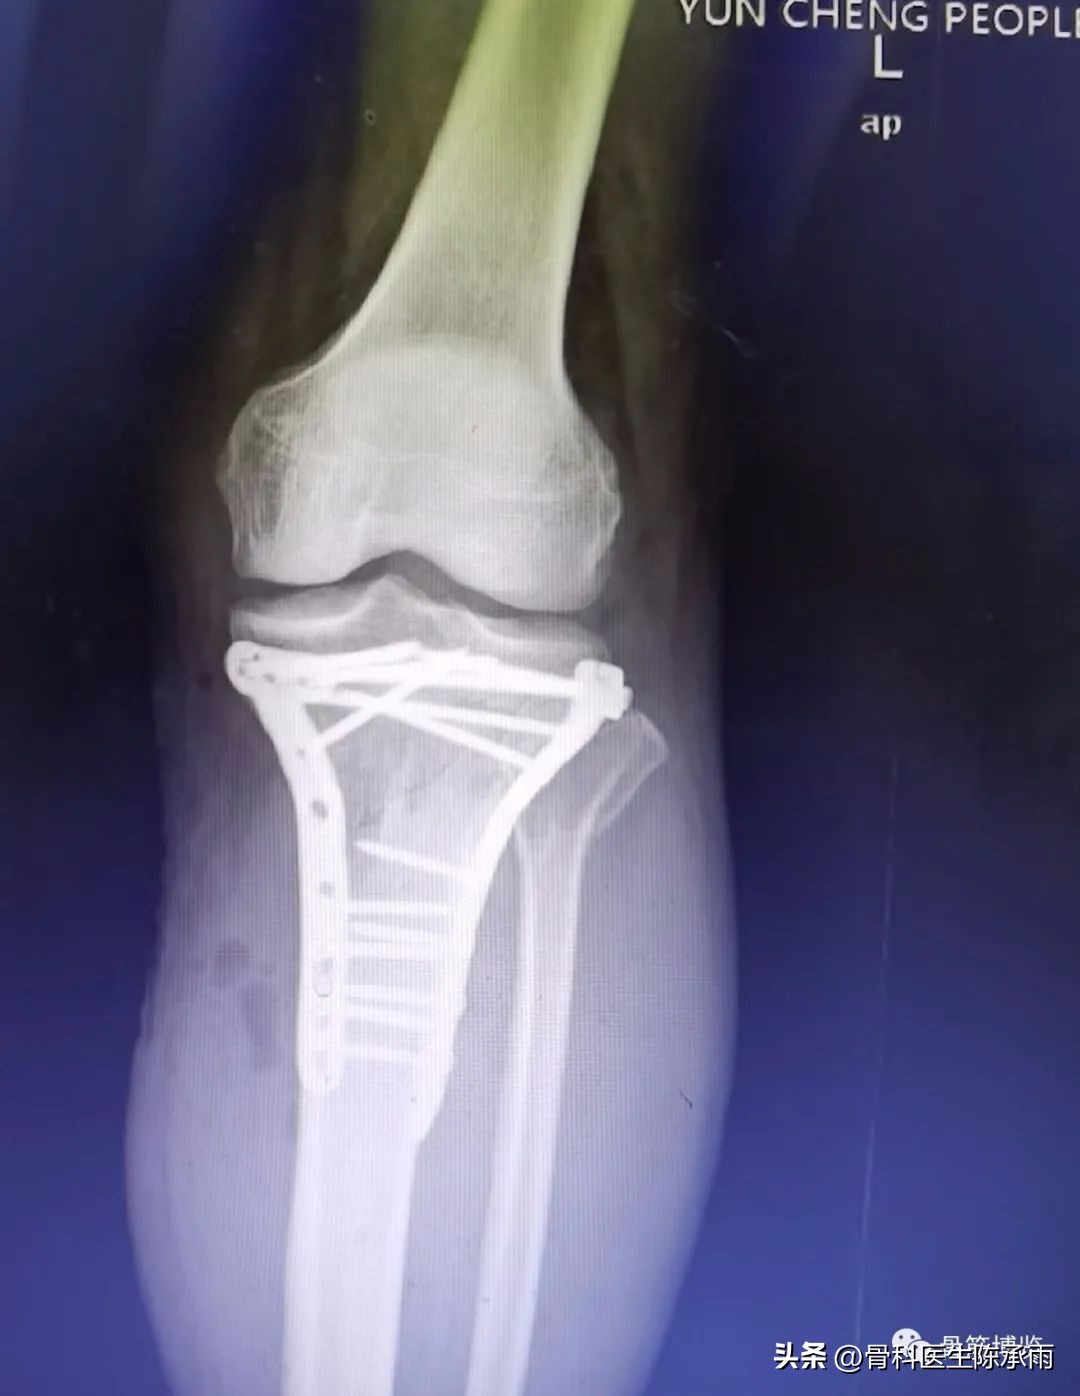

近段时间的胫骨平台骨折,没来得及详细整理

郓城县人民医院骨科诊疗技术飞速提升,开通了创伤中心绿色通道。现年手术病人达到1500余例,除常规手术外,微创手术迅速发展。关节镜,椎体成形,股骨粗隆闭合复位固定,髋膝关节置换,脊柱等手术在全市处于领先水平。